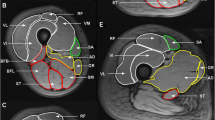

Fat and water images were used to measure muscle volume and mean fat-signal fraction (FSF) values over the whole GMed and GMin muscles, bilaterally. Gluteus muscles of each side were separately analyzed by means of a dedicated software (Myrian1; Intrasense, Paris, France) that provides a semi-automatic segmentation and automatically calculates the volume and mean pixel intensity value within the volume. A musculoskeletal radiology fellow (MM), expert in MRI data post-processing, placed the regions-of-interest (ROIs) along the edges of each muscle on each second slice of the axial water image. Care was taken to include the whole muscle and to exclude partial volume artifacts, tendinous part of the muscles and tissue outside the muscle. A validation, testing intra-observer reliability, was performed for the first ten measurements showing “almost perfect” agreement (intra-class correlation coefficient = 0.90; 95 % confidence interval, 0.78–0.95). The ROIs from the water images were exported to the fat images of the same sequence (see Fig. 1). Mean signal intensity values were collected from both, water images (Iwater) and fat images (Ifat). The FSF was obtained as follows [16]: FSF [%] = 100 × fat /(Iwater + I fat). The resulting FSF of the GMed and GMin muscles are denoted as FSFGMed and FSFGMin, respectively. The resulting volume of the GMed and GMin muscles are denoted as VGMed and VGMin, respectively. Muscle volumes were normalized to body height (muscle volume/body height2) resulting in ViGmed and ViGmin respectively.FSF and normalized volume data from both hips of each subject were averaged to mean FSFGMed, mean FSFGMin, mean ViGMed and mean ViGMin.

Water signal-only image (a) and the corresponding fat signal-only image (b) acquired in the axial plane in a 29-year-old woman. Regions of interest were traced around the margins of the GMed (green) and GMin (red) muscles in the first image (a) and then copied to the second image (b). c Coronal reconstruction obtained from fat signal-only MR images